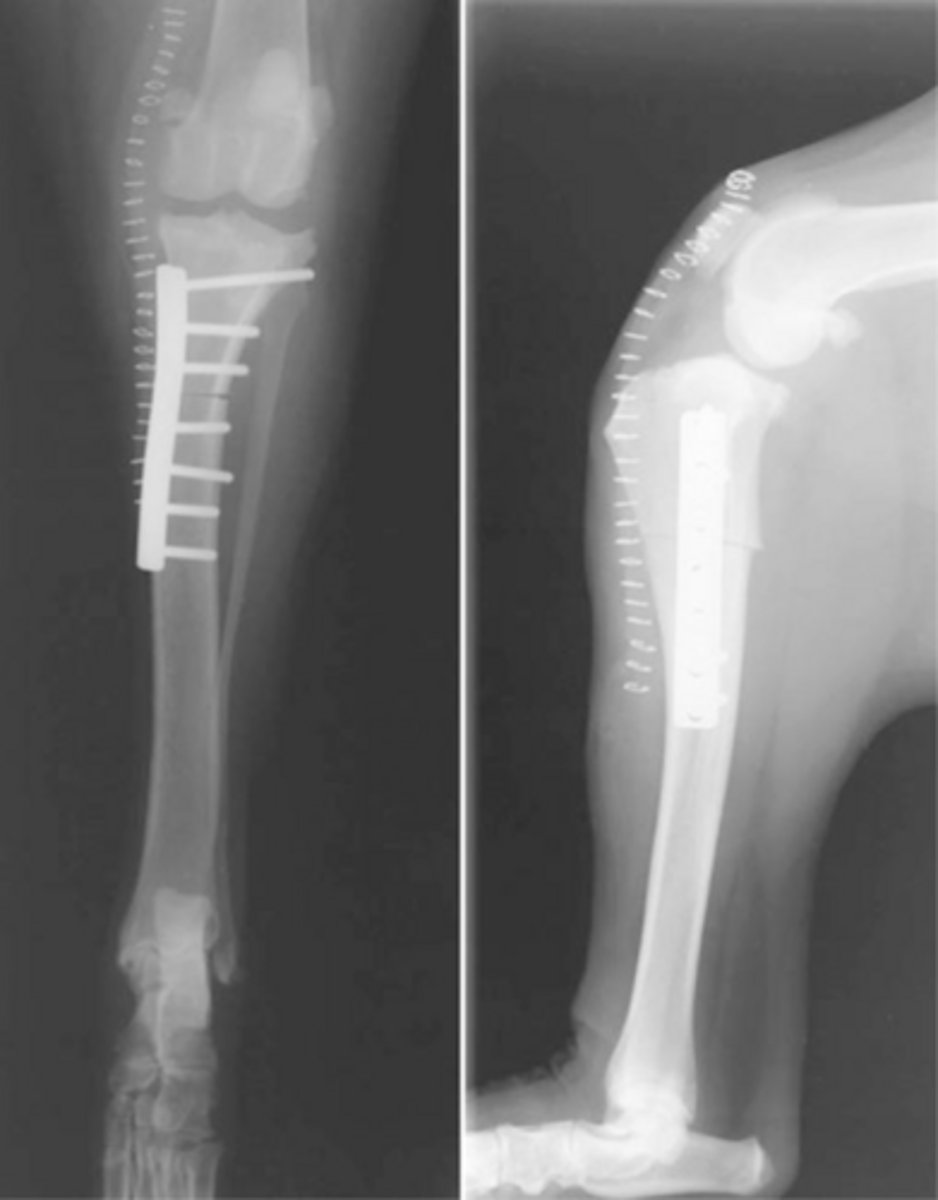

RADS for a (TWO) tibial wedge osteotomy dog

what is shown here

the lower osteotomy of the tibial wedge osteotomy (TWO) procedure has concerns due to...

CCLP and increased TPA in young dogs with open proximal tibial physes...TWO WILL NOT AFFECT PHYSES DUE TO LOWER LOCATION

the tibial wedge osteotomy (TWO) procedure was designed for what dogs...